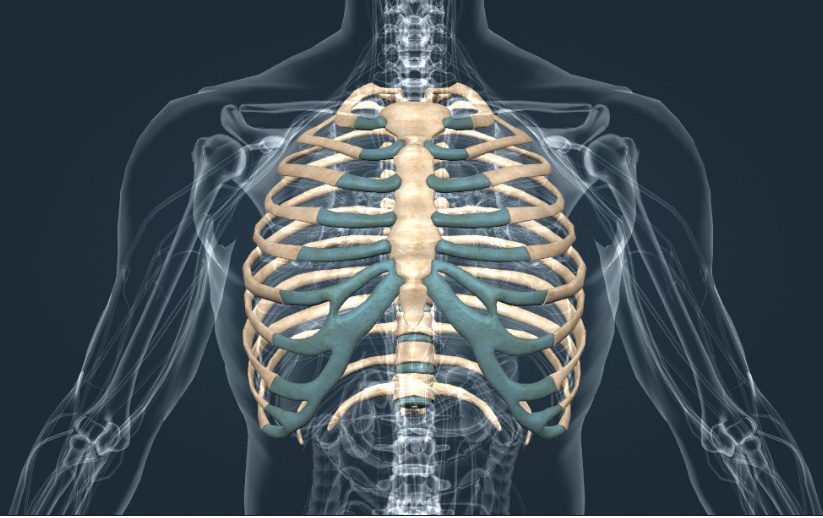

Если обратиться к базовой анатомии, то стандартное количество ребер у человека составляет 24 — это 12 пар, расположенных по обеим сторонам грудной клетки. Они формируют костную защиту для сердца, лёгких и крупных сосудов, создавая устойчивый и одновременно подвижный каркас.

Каждая дугообразная пластина состоит из двух частей — костной и хрящевой. Твёрдая основа придаёт прочность, а гибкая часть отвечает за подвижность. Первая семёрка соединена с грудиной напрямую, остальные прикрепляются косвенно или вовсе не соединяются с ней.

- Первые 7 пар — истинные. Прочно соединяются с грудиной индивидуальными хрящами, формируя жёсткий каркас.

- Следующие 3 пары — ложные. Присоединяются к грудине через общую хрящевую дугу, обеспечивая подвижность средней части грудной клетки.

- Последние 2 пары — свободные. Не соединяются с грудиной, заканчиваются в мягких тканях, легко смещаются при нагрузках.

Такая структура продумана природой: она позволяет грудной клетке двигаться при дыхании и защищает важнейшие органы от повреждений.